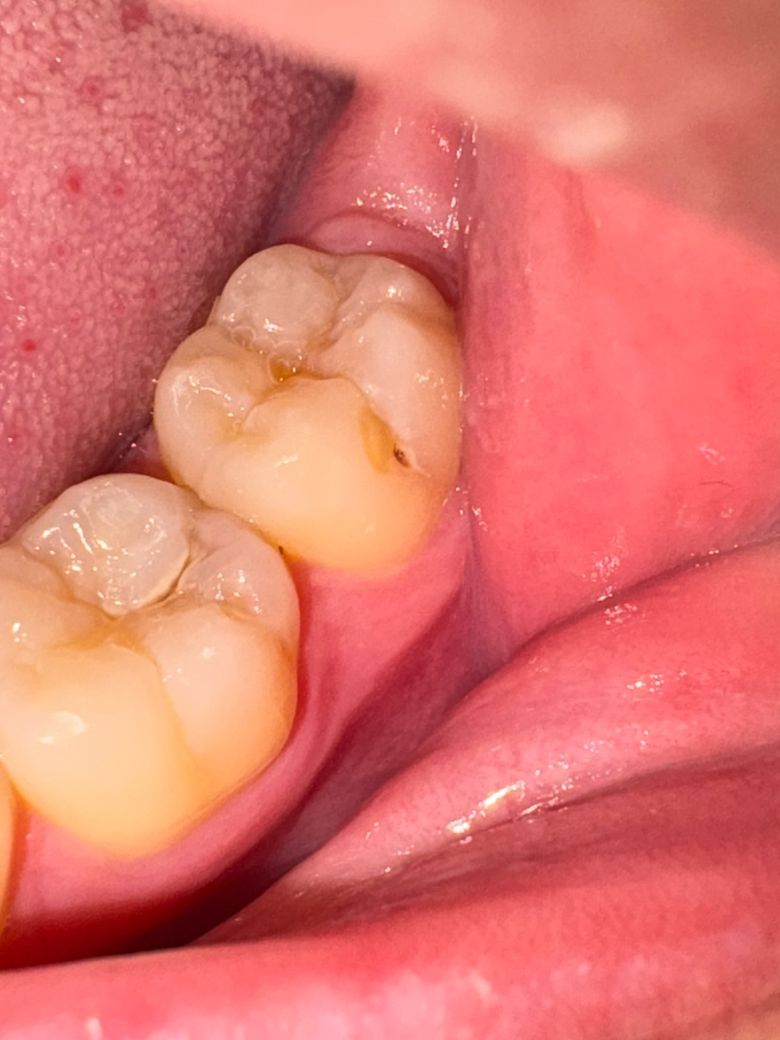

의사 선생님들 충치 관련 질문이 있습니다

질문이 3개가 있습니다 충치인거 같은데 레진으로 어금니를 때워도 될까요? 이상태에서 2개월정도 치과를 안갈시 크게 문제가 될까요? 일단 치료를 받아야하는걸까요? 답변 해주시면 감사하겠습니다

사진으로 봤을 경우에는 간단하게 레진으로 치료를 할 수 있을 것으로 생각됩니다. 채 내부에 충치로 인한 공동의 형성되어 있기 때문에 치료를 하지 않으면 해당 부위에 이물질이 들어가게 되어 충치가 더 진행될 수 있습니다.

충치가 깊게 진행이 되고 있으므로 2개월동안 방치하지 마시고 치과 가보시는 것이 좋습니다

질문이 3개가 있습니다 충치인거 같은데 레진으로 어금니를 때워도 될까요? 이상태에서 2개월정도 치과를 안갈시 크게 문제가 될까요? 일단 치료를 받아야하는걸까요? 답변 해주시면 감사하겠습니다 -> 이정도면 바로 치료 필요한 충치상태입니다 레진으로 시도해봅니댜